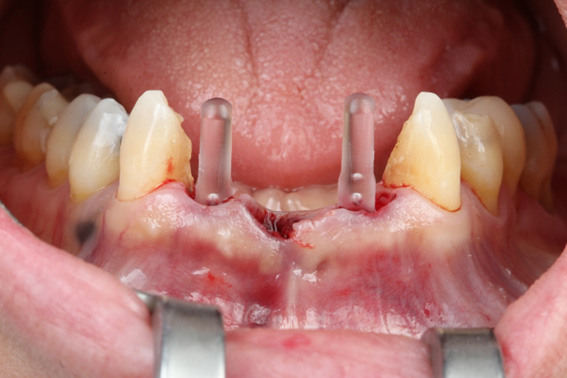

3 | Alveoli immediately after tooth extraction. Occlusal view

4 | Printed surgical guide in position for the start of drilling